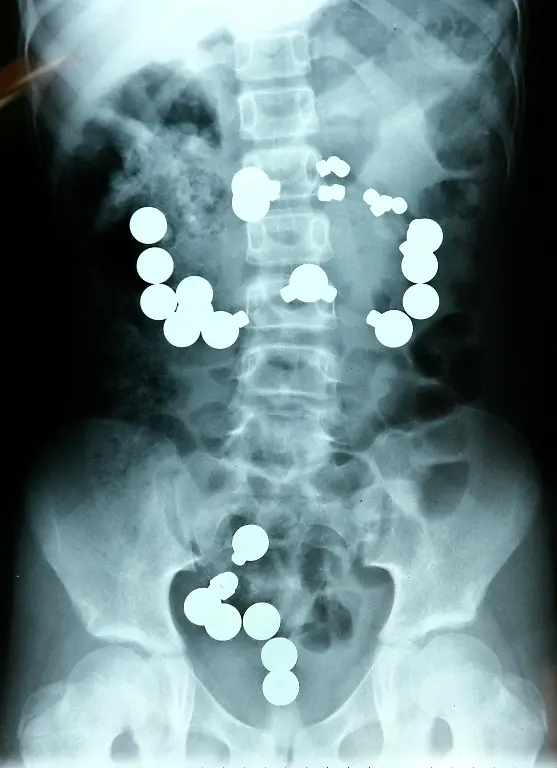

Nägel, Messer, TelefoneWas Röntgenstrahlen zum Vorschein bringen

Nicht immer zeigen Röntgenaufnahmen das, was man von ihnen erwartet. Oft kommt es zu Bildern, die selbst hartgesottene Betrachter zum Schaudern bringen - und der Wissenschaft Rätsel aufgeben.